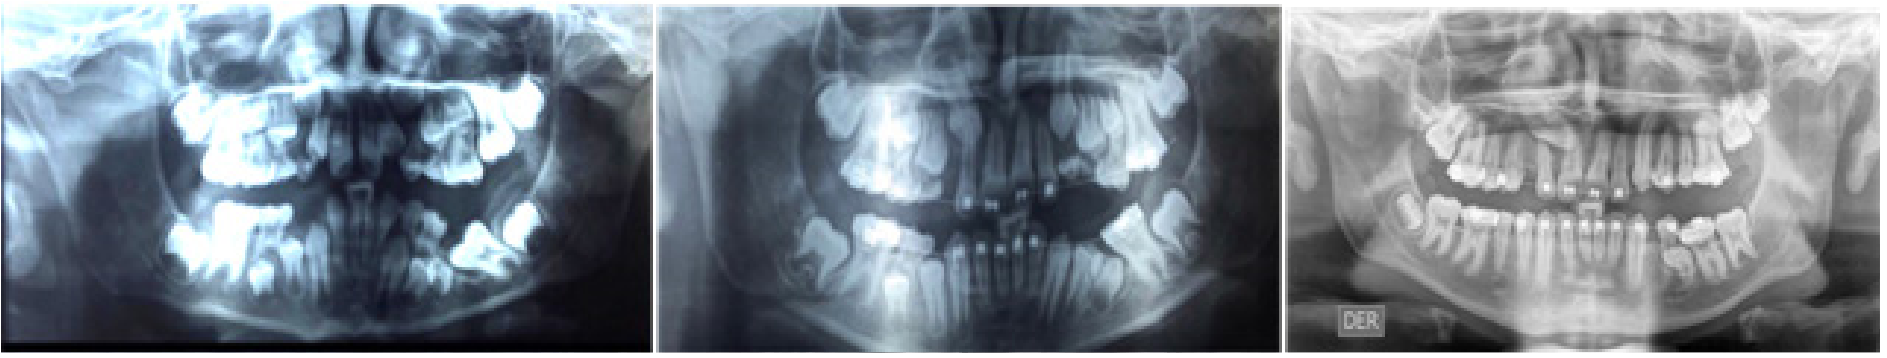

Caso 3. Paciente masculino de 15 años quien acude a consulta por falta de espacio en los maxilares. Los padres firmaron consentimiento informado. No refieren tratamiento de ortodoncia u ortopedia previo. Paciente con antecedentesdealergiaalosácaros,intervención quirúrgica de amígdalas y adenoides a los 7 años, con múltiples tratamientos por sinusitis. Alcanzó el desarrollo puberal a los 14 años y medio. Padre y madre tuvieron tratamiento de ortodoncia por apiñamientos y discrepancias estéticas. Al momento del examen diagnóstico presentó maloclusión Clase I con mordida profunda anterior, retención prolongada de los segundos molares inferiores primarios derecho e izquierdo debajo del plano oclusal inferior y debajo del plano oclusal inferior, con impactación de segundos premolares inferiores derecho e izquierdo. Además los incisivos laterales superiores se observan estrechos mesio-distalmente (Figura 3). El tratamiento consistió en: remoción del segundo molar primario inferior izquierdo y derecho retenido, terapia ortodóncica con aparatología fija .022 de Straightwire en ambos arcos dentarios.

Figura 3. Radiografía panorámica y periapicales iniciales, mostrando los segundos molares primarios retenidos en infraoclusión y la impactación de los segundos premolares inferiores.

El hermano mayor presentó canino superior izquierdo impactado. Los padres firmaron consentimiento informado. Al momento de la consulta el paciente presentó como diagnóstico: clase II con protrusión dentaria antero-superior, con ambos primeros molares superior e inferior izquierdo con un retraso importante de su erupción de 4 años. Además en la radiografía panorámica se observó impactación de canino superior derecho y de los dos premolares inferiores izquierdos. También presentó pérdida prematura del segundo molar inferior derecho primario por caries, el cual fue extraido sin colocar apropiado mantenedor de espacio, trayendo como consecuencia migración mesial del primer molar inferior izquierdo, agravando falta de espacio para la normal erupción de los premolares inferiores izquierdos. (Figura 5). El tratamiento consistió en: exposición quirúrgica del primer molar permanente superior e inferior izquierdo, terapia ortodóncica con expansión palatina rápida y aparato extra-oral de tracción cervical, combinado con ortodoncia correctiva con aparatología fija .022 de Straightwire.

Caso 6. Paciente femenina de 14 años de edad que se presenta a consulta por problemas de retroposición en la mandíbula. Al interrogatorio los padres refieren presencia de alteración de la hormona tiroidea y tratamiento con Eutirox. No reportó tratamiento de ortodoncia u ortopedia previo. Refirió haber tenido alterado el recambio dentario en todos los dientes y extracción de incisivos primarios por odontopediatra, para facilitar la erupción de los incisivos permanentes. La A madre tuvo tratamiento para maloclusión Clase II con aparato extraoral de tracción baja, el hermano presentó Clase II y recibió tratamiento con Bionator. La madre firmó consentimiento informado. Al momento del diagnóstico inicial la paciente presentó maloclusión Clase II con deficiencia de espacio importante y apiñamiento en ambos arcos dentarios. El segundo premolar inferior derecho era muy ancho mesio-distalmente (anómalo), produciendo una discrepancia de Bolton posterior. Tuvo retención prolongada de molares primarios superiores e inferiores, con presencia además de molares primarios supernumerarios. Se realizó la extracción de los molares primarios, la extracción de los molares primarios supernumerarios y se expusieron quirúrgicamente los seis (6) premolares impactados superiores e inferiores, llevándolos al arco dentario mediante la utilización de aparatología fija de Straightwire .022 en ambos arcos dentarios. (Figura 6)

Figura 5: Radiografías panorámica inicial y dos radiografías panorámicas de progreso, donde se evidencia la impactación de los primeros molares superiores e inferiores, la inclinacion mesial del primer molar inferior izquierdo asociada a la pérdida prematura del segundo molar primario inferior izquierdo, produciendo impactación a su vez de los premolares inferiores izquierdos.

Figura 6: Radiografía panorámica inicial (A) y radiografía panorámica de progreso (B), luego de extracción de los molares primarios retenidos y molares primarios supernumerarios.